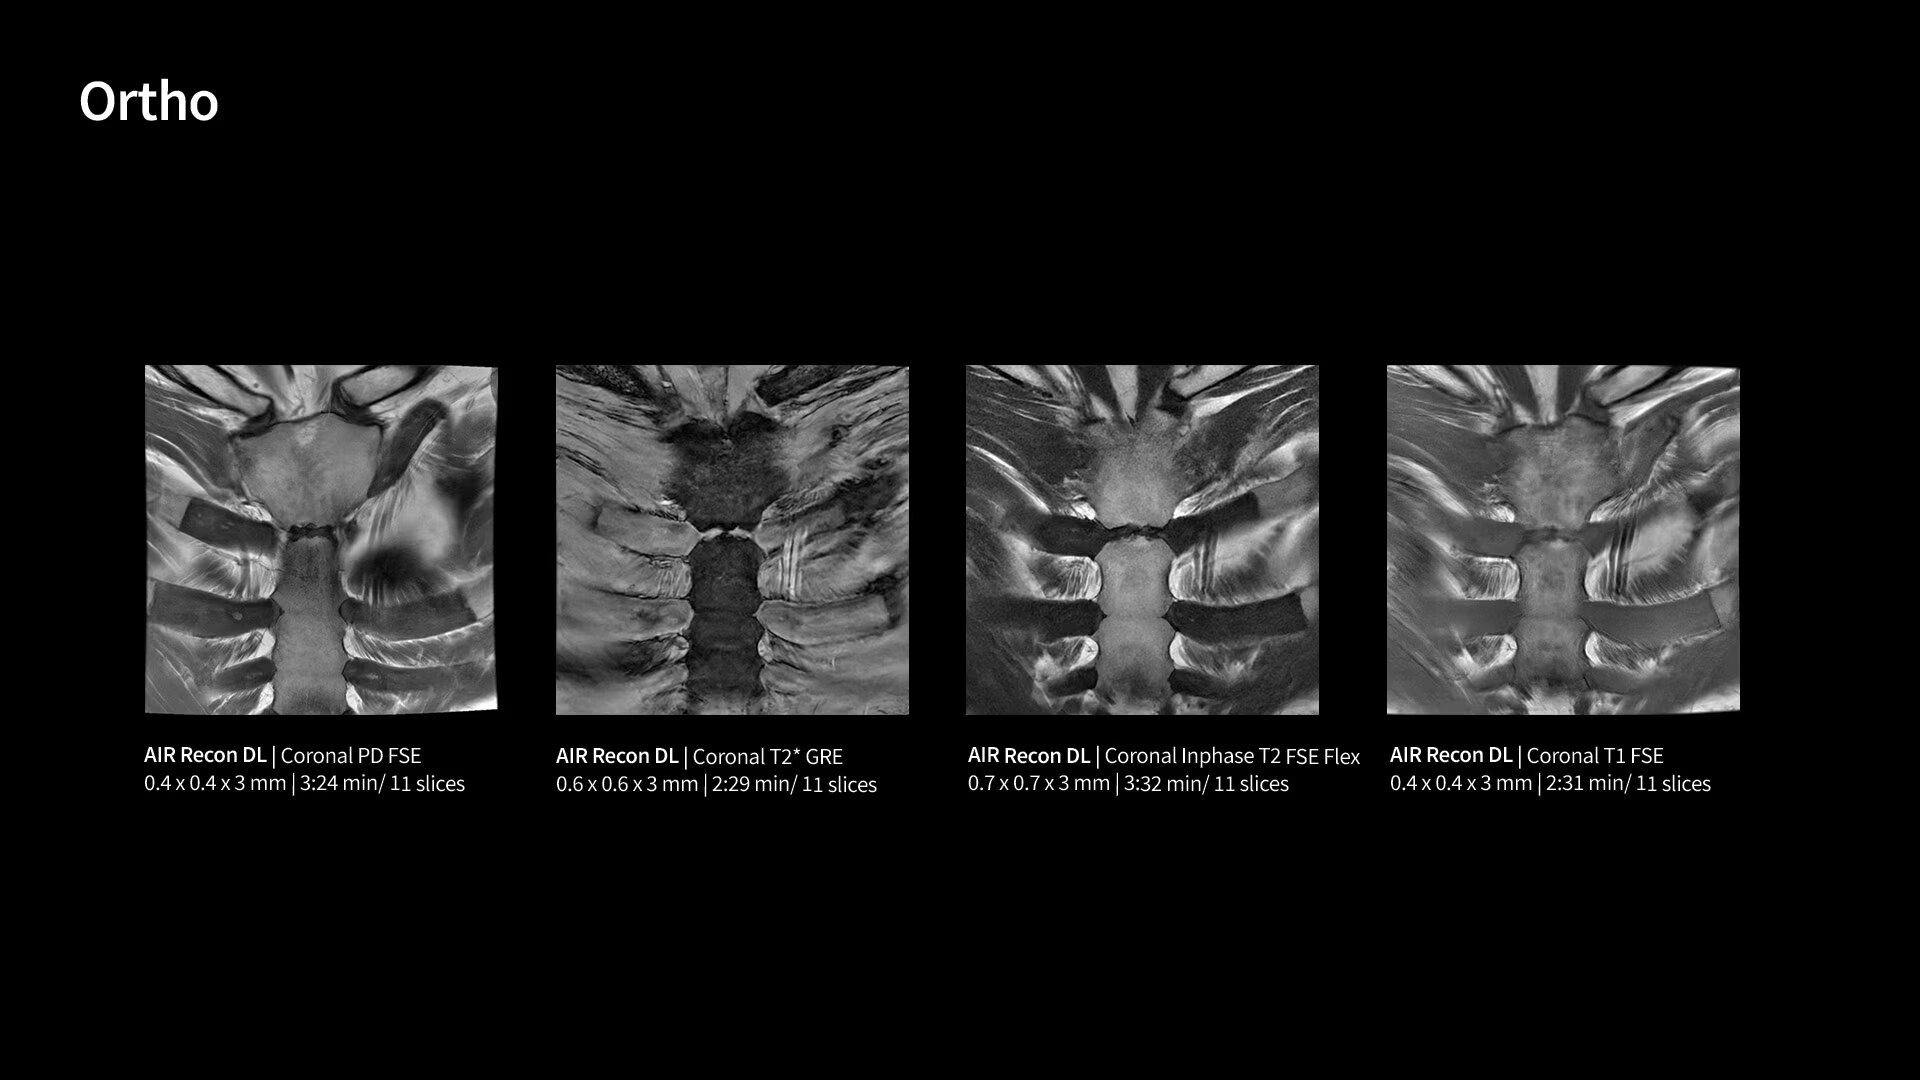

With GE HealthCare's comprehensive suite of deep-learning solutions integrated into SIGNA Sprint, you can unlock the full potential of your MRI system. No need for complicated patient setups or imaging protocols. The exceptional intelligence of our AI solutions offer multiple benefits, with AIR Recon DL giving pin-sharp images, Sonic DL accelerating scans up to 12x, and AIR x enabling automated slice placement. All helping to enhance your department’s workflow efficiency, increase patient throughput, and get the diagnostic clarity you need, faster.¹ Meaning you can spend more time on what truly matters—personalized patient care, enabling optimized treatment plans and treatment response monitoring—ultimately, supporting better clinical outcomes.